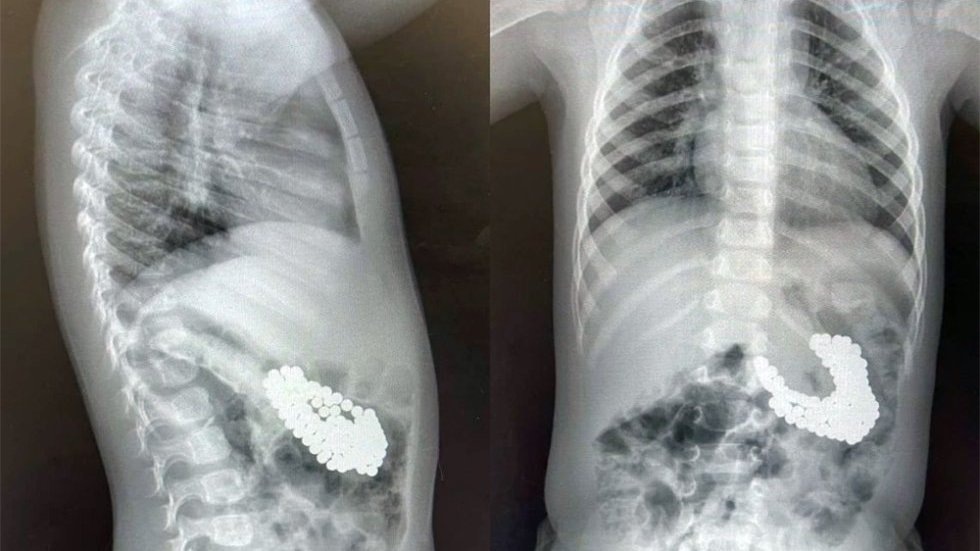

Врачам пришлось оказывать срочную помощь полуторагодовалому ребенку из Московской области, который проглотил батарейку и 130 магнитов. Как сообщает пресс-служба регионального Минздрава, мальчик был доставлен в детский клинический центр имени Л.М. Рошаля. Врачи отметили, что магниты нужно удалять как можно скорее, так как они могут спровоцировать ожоги, повреждения внутренних органов, некроз тканей и кровотечение. «Мы удалили из желудка ребенка 130 магнитов и батарейку. Магниты сцепились друг с другом, что вызвало повреждения слизистой и образование язвы. Нужно было действовать быстро. С помощью эндоскопических инструментов – «Сачка», зажима «Аллигатор» и «Корзины Дормиа» – мы провели гастроскопию и извлекли все инородные предметы», – сообщил заведующий эндоскопическим отделением Александр Иноземцев. Некоторые магниты сцепились в кишечнике, их пришлось извлекать с помощью лапароскопической операции. На данный момент мальчик чувствует себя хорошо. Ребенок выписан для амбулаторного наблюд

Фото: минздрав Московской области